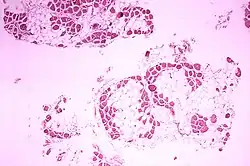

Histopathologisches Bild eines Querschnitts aus dem Wadenmuskel (Musculus gastrocnemius) eines Patienten, der an Muskeldystrophie Typ Duchenne starb. Das Bild zeigt einen ausgeprägten Umbau des Muskelgewebes mit Einlagerung von Fettgewebe

In der Myologie (Muskellehre) bezeichnet die Pseudohypertrophie eine Zunahme des Muskelvolumens durch Fettgewebseinlagerung oder bindegewebigen Umbau der Muskulatur. Die Größenzunahme des Muskels kommt also nicht durch eine Vergrößerung der Muskelzellen zustande, wie es bei der Hypertrophie der Fall ist.